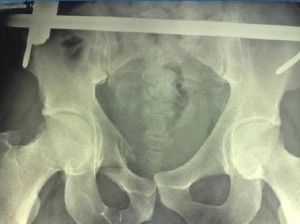

Диагностика

Если есть подозрения, что сломана кость, необходимо пройти ряд диагностических процедур. Основный метод диагностики – рентгенография в двух проекциях. Но окончательное решение по поводу диагноза врач может принять после дополнительного обследования: